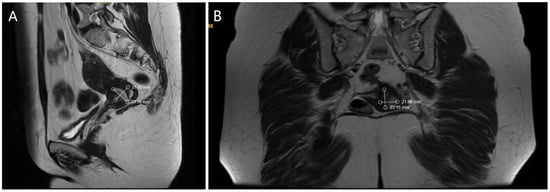

Ultrasound examination of the abdomen and pelvis revealed no abnormal findings, and lung radiography was normal. Preoperative magnetic resonance imaging (MRI) identified an infiltrative tumor measuring 23.69 × 21.70 mm, as demonstrated in Figure 1A,B.

Figure 1.

(A). MRI—Sagittal section of the tumor formation (B). MRI—Coronal section of the tumor formation.